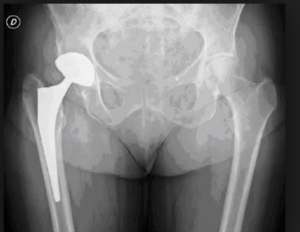

L’arthrose de la hanche est la plus répandue et celle dont on entend le plus parler. Cette localisation de l’arthrose est surtout connue à cause des prothèses qui sont, de nos jours, très fiables. Mais !

Mais on entend peu parler de l’avant… Pourtant avant la prothèse, les patients souffrent pendant de longues années alors qu’une kinésithérapie bien menée pourrait empêcher d’en arriver là. En effet, comme je l’ai expliqué plus haut, dès le début de la pathologie (et avant tout signe radiologique), le patient décrit des douleurs mécaniques et un examen minutieux de sa hanche peut mettre en évidence un schéma caractéristique aux tests passifs : la rotation interne, l’abduction et la flexion sont plus limitées que l’extension, alors qu’il y a peu de limitation de l’adduction et de la rotation externe ( peu importe l’ampleur des limitations.)

Les prothèses de hanches sont très fiables et les gens remarchent en quelques jours (quasiment pas de rééducation après).